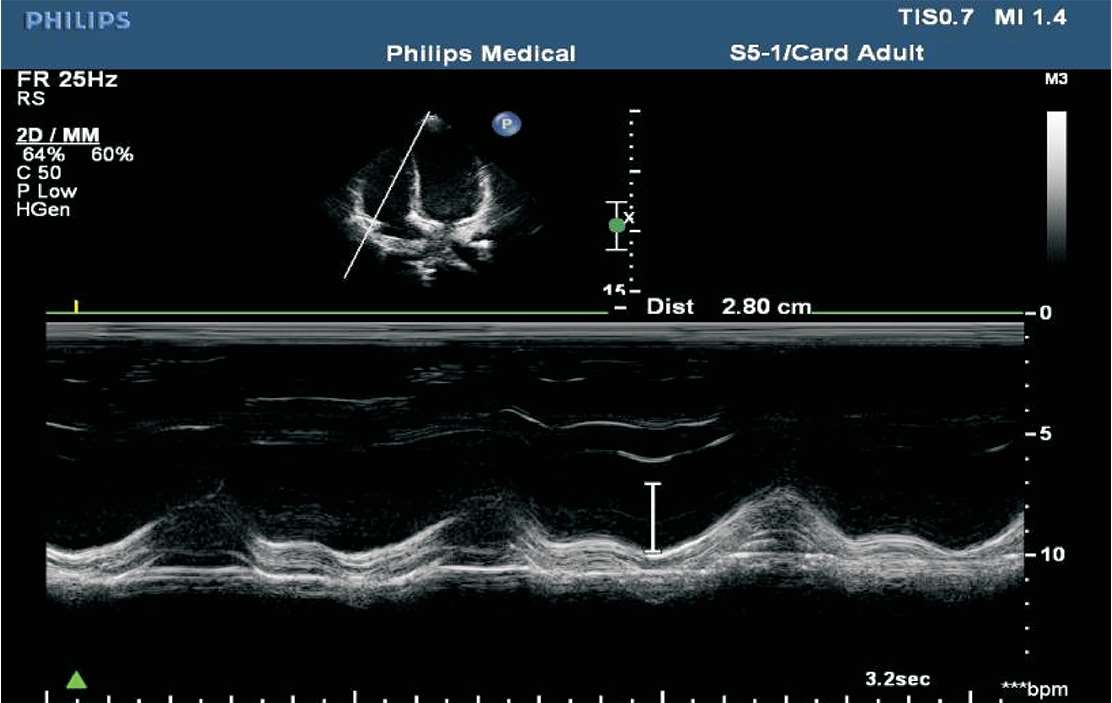

(1)M型超声心动图,适用于左心室无节段性运动异常者。取标准胸骨旁左心室长轴切面,取样线置于二尖瓣腱索水平,测量左心室舒张末期内径(LVD)与收缩末期内径(LVS),根据测量内径推算左心室舒张末期及收缩末期的容量,再根据左心室舒张末期容量及收缩末期容量的变化求出心输出量(见图1-36)。

图1-36 左心室波群

(1)三尖瓣环收缩期位移(TAPSE)。用M型超声测得三尖瓣外侧瓣环的运动曲线,在曲线上测量舒张末期最低点至收缩末期最高点之间的距离,正常时≥16 mm,<16 mm时考虑为右心室收缩功能降低(见图1-41)。

图1-41 三尖瓣环收缩期位移